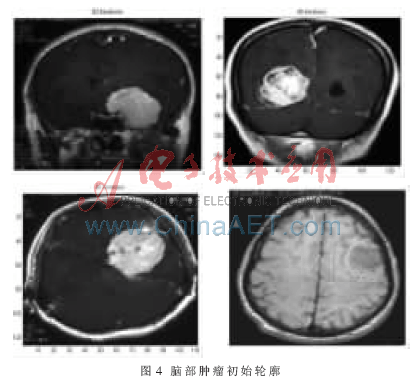

根據(jù)初始輪廓模型,應(yīng)用改進(jìn)主動(dòng)輪廓模型提取腦部腫瘤邊緣。圖4為一組勾畫了腦部腫瘤初始輪廓的MR圖像,圖5為在圖4的初始輪廓下,基于改進(jìn)主動(dòng)輪廓模型提取的腫瘤邊緣。從圖5可以看出,基于改進(jìn)主動(dòng)輪廓模型提取腦部腫瘤邊緣不僅能夠接近真實(shí)邊緣的凹陷處,而且快速收斂到物體的真實(shí)邊緣。實(shí)驗(yàn)結(jié)果證明,主動(dòng)輪廓模型中改進(jìn)的一階連續(xù)性能量是有效的,使初始輪廓能夠接近物體凹部,同時(shí)很好地保持了個(gè)點(diǎn)之間的連續(xù)性,改變了原始主動(dòng)輪廓模型的非凸性性質(zhì)。